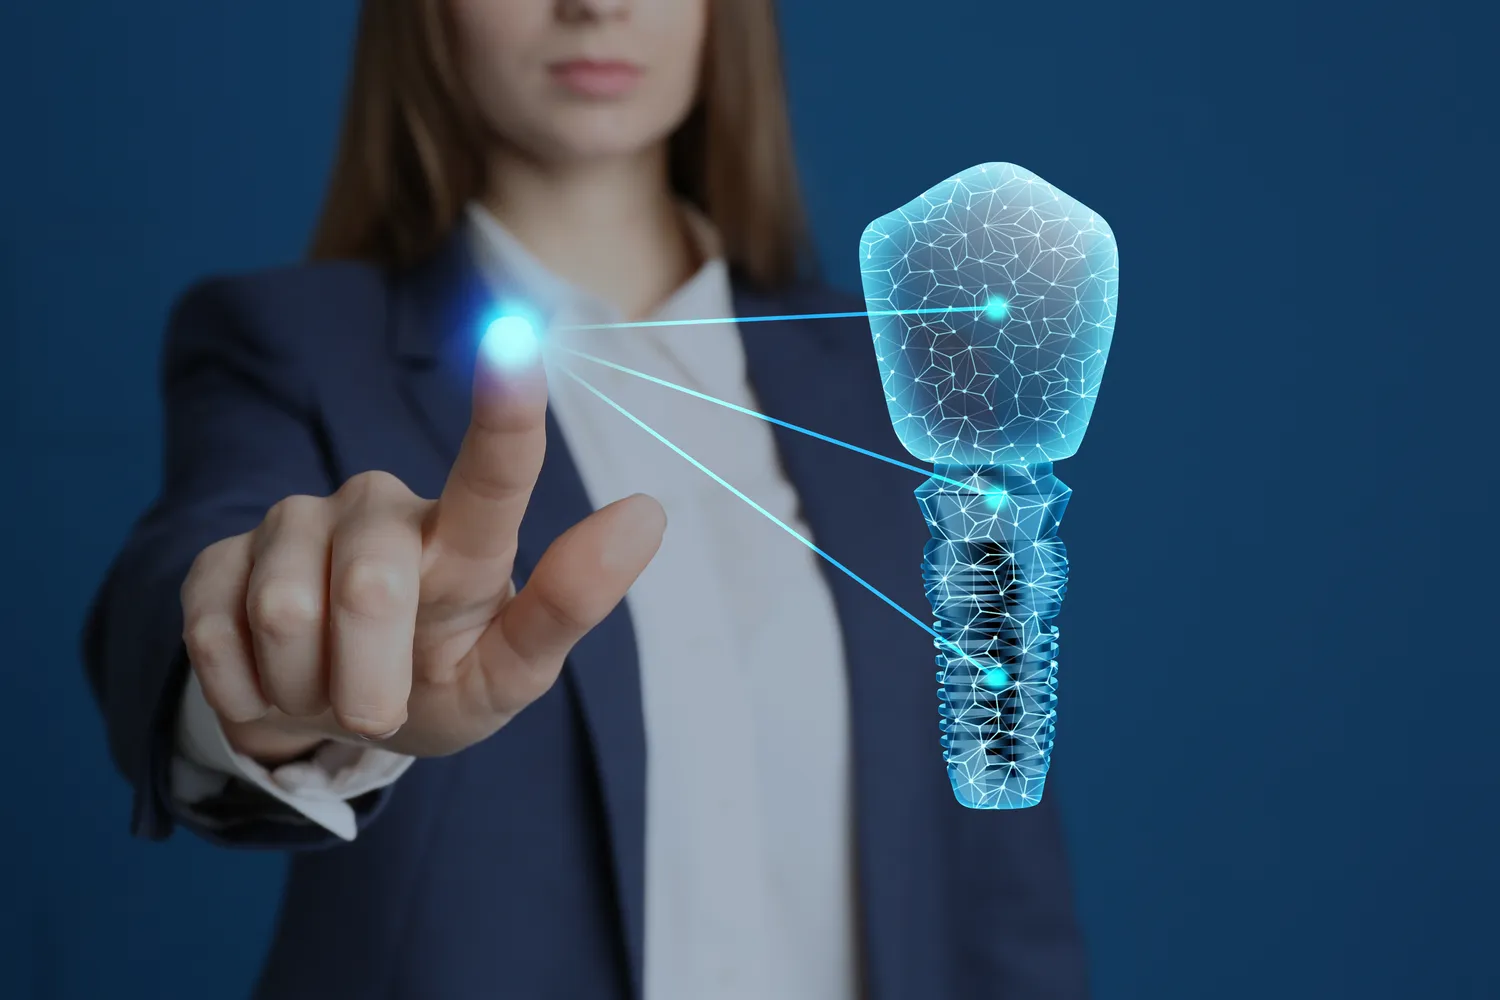

Protetyka stomatologiczna Lublin

Protetyka stomatologiczna w Lublinie to dziedzina medycyny, która zajmuje się odbudową zębów oraz przywracaniem funkcji żucia i estetyki u pacjentów, którzy utracili swoje naturalne zęby. W ramach tej specjalizacji stosuje się różnorodne materiały oraz techniki, aby stworzyć protezy, mosty czy korony, które są dostosowane do indywidualnych potrzeb pacjenta. Protetyka ma na celu nie tylko poprawę… Read more

Protetyka stomatologiczna zębów Szczecin

Protetyka stomatologiczna w Szczecinie to dziedzina, która zajmuje się odbudową zębów oraz przywracaniem funkcji żucia i estetyki u pacjentów. Wiele osób boryka się z problemem utraty zębów, co może wynikać z różnych przyczyn, takich jak próchnica, urazy czy choroby dziąseł. W Szczecinie dostępne są różnorodne usługi protetyczne, które pozwalają na indywidualne podejście do każdego pacjenta.… Read more

Protetyka Lublin

Protetyka w Lublinie to dziedzina stomatologii, która zajmuje się odbudową zębów oraz przywracaniem funkcji żucia i estetyki u pacjentów. W Lublinie dostępnych jest wiele gabinetów stomatologicznych, które oferują różnorodne usługi protetyczne, takie jak korony, mosty, protezy czy implanty. Wybór odpowiedniego specjalisty jest kluczowy dla uzyskania satysfakcjonujących efektów. Warto zwrócić uwagę na doświadczenie lekarza oraz opinie… Read more

Protetyka 3d Lublin

Protetyka 3D w Lublinie to nowoczesna dziedzina stomatologii, która wykorzystuje zaawansowane technologie do tworzenia protez zębowych. Dzięki zastosowaniu druku 3D, proces produkcji protez stał się znacznie szybszy i bardziej precyzyjny. W tradycyjnej protetyce często korzystano z odlewów, które mogły być czasochłonne i wymagały wielu wizyt u dentysty. W przypadku protetyki 3D, lekarze stomatolodzy mogą skanować… Read more

Protetyka stomatologiczna Warszawa

Protetyka stomatologiczna w Warszawie to dziedzina medycyny, która zajmuje się odbudową zębów oraz przywracaniem funkcji żucia i estetyki u pacjentów. W stolicy Polski znajduje się wiele gabinetów stomatologicznych oferujących szeroki wachlarz usług protetycznych, od protez całkowitych po mosty i korony. Warto zwrócić uwagę na to, że protetyka nie tylko poprawia wygląd uśmiechu, ale również ma… Read more